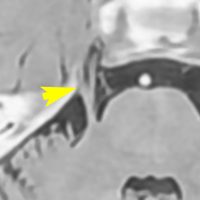

左側の写真は,顔面神経の根っこを前下小脳動脈が圧迫しているところです。矢印が示すのは,脳から顔面神経が出たところ(REZ レズ)です。ここが圧迫されないと顔面けいれんは起こりません。右側の写真は,動脈をよけて顔面神経のREZを解放したところです。長い間の圧迫でちょっとヘコんでいます。これが最も多いタイプです。